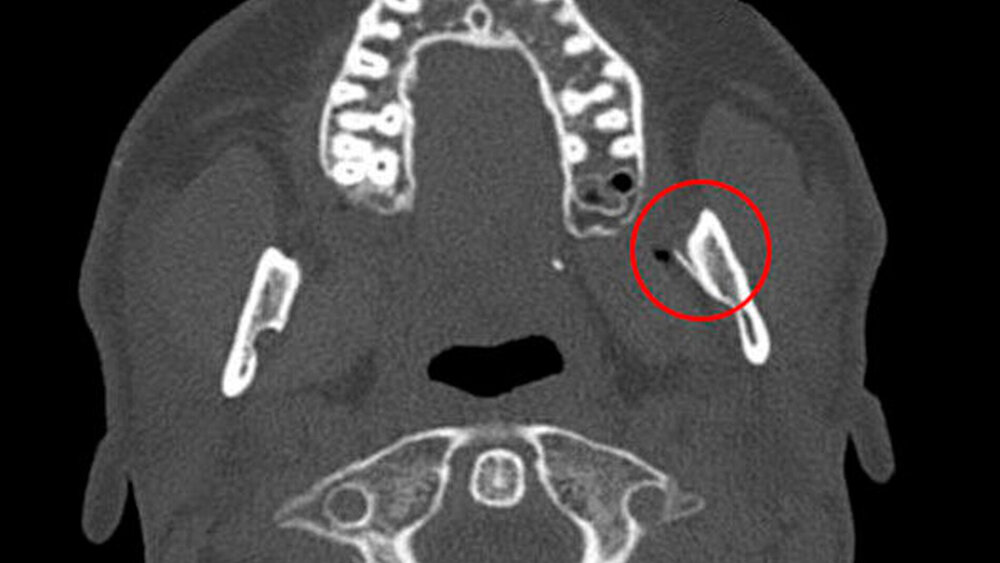

Hier zeigte sich als Corpus alienum die frakturierte Kanüle in unveränderter Position im Bereich der medialen Seite des aufsteigenden Unterkieferastes auf Höhe des Foramen mandibulae zwischen Unterkieferknochen und Musculus pterygoideus medialis (Abbildungen 2, 3).

Forciert werden kann ein solches Geschehen gerade in der beschriebenen Lokalisation durch Schluck-, Sprech- und Kaubewegungen sowie Würge- oder Hustenreiz. Als dreidimensionale Bildgebung eignet sich die Computertomographie (CT). Sie bietet den Vorteil der sofortigen Verfügbarkeit im Rahmen der Notfalldiagnostik innerhalb der Klinik. In Bezug auf die Darstellung des Weichteilschattens und der möglichen Gabe eines ergänzenden Kontrastmittels bietet sie einen entscheidenden Vorteil gegenüber der Digitalen Volumentomographie (DVT). Nachteilig ist demgegenüber die erhöhte Strahlenbelastung.